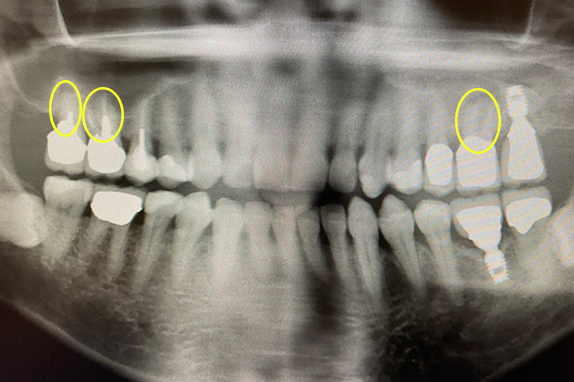

CASE 01 歯周再生治療

-

- 主訴

- 歯がグラグラで噛めない

-

- 回数期間

- 5回 約1年

-

- 治療法

- 歯周再生治療

-

- 治療費用

- 約17万円(税抜)

歯がグラグラで噛めないという主訴の患者様に歯周再生治療を用いて改善したケースです。レントゲン写真をみると術前は歯肉の退縮が見られるが、術後は歯肉の退縮が改善しています。

<リスク・副作用>

手術後は腫れ、痛み、痺れなどの副作用が生じる場合があります。